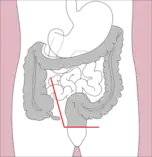

- Right hemicolectomy and left hemicolectomy refer to the resection of the ascending colon (right) and the descending colon (left), respectively. When part of the transverse colon is also resected, it may be referred to as an extended hemicolectomy.[5]

Right hemicolectomy

Right hemicolectomy Right extended hemicolectomy

Right extended hemicolectomy Left hemicolectomy

Left hemicolectomy Extended left hemicolectomy

Extended left hemicolectomy - Transverse colectomy is also possible, though uncommon.